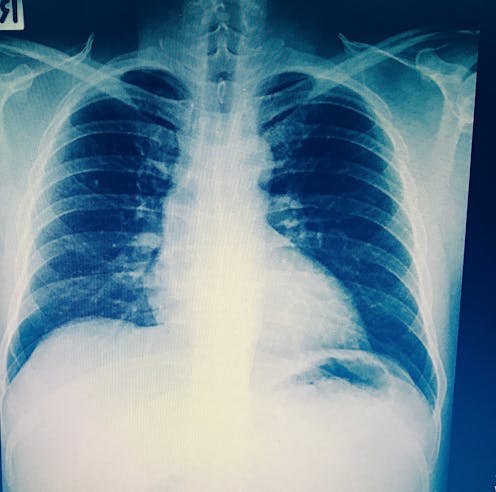

Tuberculosis (TB) is a lung disease caused by the bacterium Mycobacterium tuberculosis. It’s transmitted through air droplets when an infectious person coughs or sneezes. The disease can be treated, but it’s a long process with the drugs that are currently available. It remains a major health problem: globally, about 1.6 million died from it in 2017.

Treating TB is only one part of the puzzle. Proper, timely diagnosis and a good understanding of the disease’s progression in an individual patient are also important.

The disease is currently diagnosed in several ways. These include viewing a sputum sample under a microscope; through a skin test; or through a blood test.